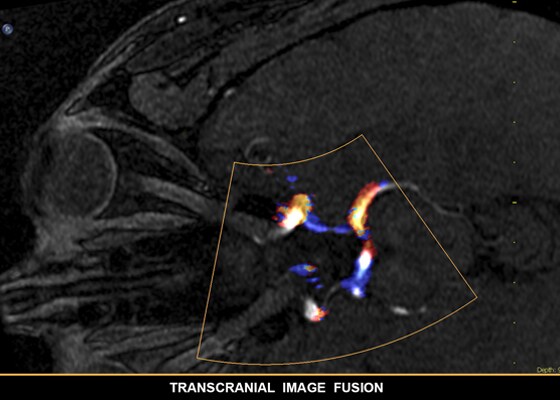

Anatomical Intelligence is used in Philips imaging solutions such as EPIQ, Affiniti, and EchoNavigator. Already today it is providing clinicians with sophisticated, yet easy-to-use processing tools, and helping them quickly and more confidently identify anatomy and anomalies, assess disease states, determine treatment, and guide interventions.